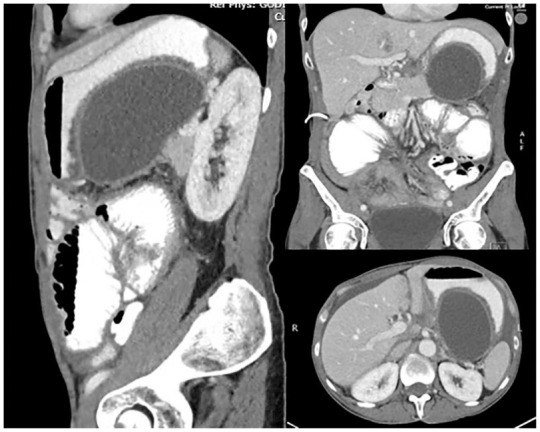

Endoscopic ultrasound-guided drainage of loculated malignancy-related ascites has been reported in limited case series with success in achieving symptomatic relief. In this case report, we detail the successful drainage of a loculated paragastric ascites with insertion of a lumen-apposing metal stent (LAMS) in a patient diagnosed with metastatic ovarian cancer.

Abstract Image